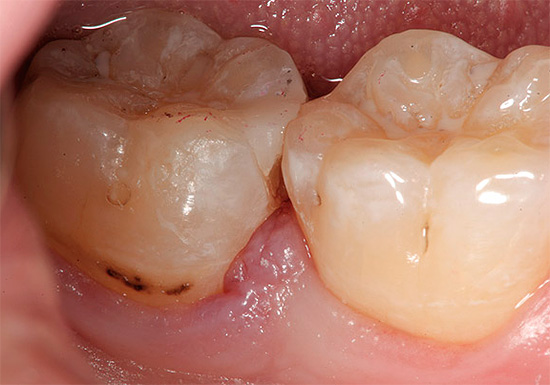

Se houver um orifício no esmalte (cavidade), definitivamente não será possível curar um dente sem obtê-lo. Em muitos casos, essas lesões de cárie que só podem ser tratadas por um dentista se apresentam como manchas marrons ou pretas distintas.

Isso é especialmente verdadeiro para fissuras, onde esses pontos às vezes podem ser muito pequenos e não se incomodam com nada, e é por isso que muitos não os percebem como um problema sério. Enquanto isso, a área da lesão sob essa mancha já pode penetrar profundamente na dentina.

Devido ao pequeno tamanho das áreas escuras na área da fissura, muitos acreditam que esses pontos podem simplesmente ser clareados ou lixados em casa, e a cárie dentária como se isso fosse curado. De fato, essa mancha é apenas um sinal de que a cárie não pode ser curada sem preenchimento.

Não faz sentido tentar remover os tecidos escuros dos dentes cariados por métodos mecânicos por conta própria. Pode parecer que, se você limpar as áreas escuras com uma agulha ou triturá-las com algum material abrasivo (lixa, lima), o próprio espaço limpo ficará "cheio". Este é um erro grave: a cárie nunca se recuperará por si própria e, com uma alta probabilidade, o tecido dentário nessa área continuará se deteriorando após a limpeza.